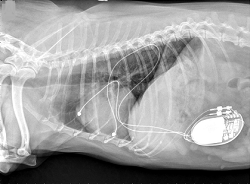

The most effective long-term care for symptomatic second-degree AV block and third-degree AV block cases has been found to be the surgical insertion of an artificial pacemaker (right, above).

(See an x-ray of her at left.) Because of the severely enlarged right chambers, dual chamber pacing

She was treated with a permanent artificial cardiac pacemaker and, due

to the severe structural heart disease and heart failure present, a dual

chamber pacemaker system was recommended in attempt to optimize cardiac

performance by maintaining AV synchrony and heart rate variability.

Because of the severely enlarged right chambers, dual chamber pacing

with epicardial lead placement was recommended. The dog was rechecked at

7 months following implantation, and the owners reported complete

resolution of clinical signs and an increase in the dog’s activity. The

pacemaker required no change in settings.

Permanent dual chamber epicardial pacemaker implantation in two dogs with complete atrioventricular block. Christian Weder, Eric Monnet, Marisa Ames, Janice Bright. J. Vet. Cardiol. June 2015; doi: 10.1016/j.jvc.2014.11.002. Quote: Between November 2013 and December 2013, two dogs with complete atrioventricular (AV) block had a permanent, dual chamber epicardial pacing system implanted. Steroid-eluting unipolar, button-type epicardial leadsa were sutured to the right atrial appendage and right ventricular wall via a right thoracotomy in both dogs. The pacemakers were programmed in VDD mode. Permanent dual chamber epicardial pacemaker implantation was successful in both dogs with no intra-operative complications. One dog had an acute onset of neurologic signs two days post-operatively that resolved within 24 h. Both dogs have had complete resolution of the clinical signs related to the bradyarrhythmia, and one dog has had complete resolution of chylothorax. One dog had a major lead complication characterized by intermittent loss of capture that resolved by increasing the pacemaker output. Based on the outcome of these two cases, implantation of permanent dual chamber epicardial pacing systems is possible in dogs providing an alternative to dual chamber transvenous systems. ... Case 1: A seven-year-old spayed female Cavalier King Charles spaniel was referred to the cardiology service at the Colorado State University Veterinary Teaching Hospital for evaluation of an approximately four-day history of lethargy, exercise intolerance, and decreased appetite with an inappropriate bradycardia (heart rate = 40 bpm). Initial diagnostics included an ECG, echocardiogram, Doppler blood pressure, complete blood count, biochemical profile, thoracic radiography, and urinalysis. Testing for heartworm, Lyme disease, Anaplasma phagocytophilum, Ehrlichia canis, Ehrlichia ewingii and Anaplasma platys was also done. The ECG showed third-degree atrioventricular (AV) block with a ventricular escape rhythm that was unresponsive to atropine (0.04 mg/kg SQ; no AV nodal conduction noted post atropine). The Doppler echocardiogram showed degenerative mitral valve disease (ACVIM stage B2), degenerative tricuspid valve disease with severe tricuspid regurgitation, severe right atrial and right ventricular dilation, and moderate pulmonary hypertension. ... Treatment with a permanent artificial cardiac pacemaker was advised and, due to the severe structural heart disease and heart failure present, a dual chamber pacemaker system was recommended in attempt to optimize cardiac performance by maintaining AV synchrony and intrinsic heart rate variability. Furthermore, the risk of lead dislodgement, intracardiac thrombus, and myocardial perforation were deemed considerable with transvenous pacing due to the severe right ventricular dilation. For these reasons, dual chamber pacing with epicardial lead placement was recommended. ... The dog was rechecked again at 7 months postimplantation and the owners reported complete resolution of clinical signs and an increase in the dog’s activity. Interrogation of the pacemaker at this time showed appropriate atrial and ventricular sensing as well as appropriate pacing and capture. No pacemaker settings were changed. Thoracic radiographs obtained at this visit confirmed correct position of both leads (Fig. 1) [See Figure 1, below].